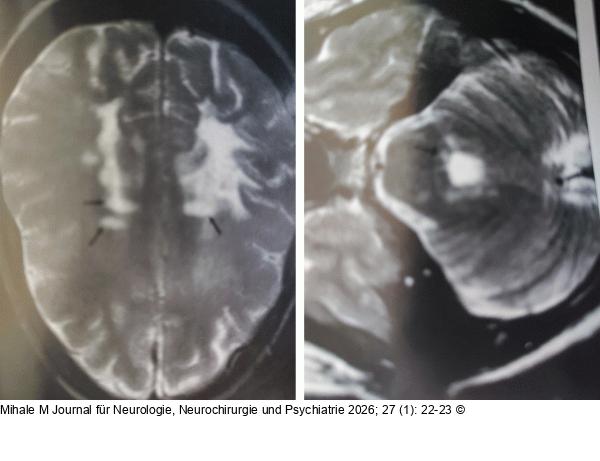

Abbildung 1: MRT MRT: T2-gewichtete Läsionen supratentoriell, infratentoriell und im zervikalen Rückenmark |

MRT: T2-gewichtete Läsionen supratentoriell, infratentoriell und im zervikalen Rückenmark |